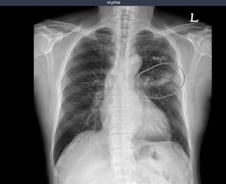

의료 인공지능(AI) 기업 뷰노가 최근 우즈베키스탄 국군중앙병원을 포함해 주요 군 병원 5곳에 인공지능 기반 X선 판독 보조 솔루션 2종을 공급했다고 23일 밝혔다. 우즈베키스탄 군 병원에 도입된 솔루션은 뷰노의 AI 기반 상지 엑스레이 판독 보조 솔루션 '뷰노메드 익스트리미티 엑스레이'와 이동형 엑스레이 장비에 AI 기반 흉부 엑스레이 판독 보조 솔루션 '뷰노메드 체스트 엑스레이'를 탑재한 패키지 제품이다. 두 제품 모두 뷰노가 과학기술정보통신부 및 정보통신산업진흥원(이하 NIPA)이 추진하는 '군 의료영상 데이터 기반 인공지능 판독 시스템 고도화 및 실증 사업(이하 군 의료 사업)'의 일환으로 개발한 제품이다. 격오지를 중심으로 현장 의료서비스가 가능하도록 설계돼 의료 인프라가 낙후한 지역에서도 진단 편차를 줄이고 의료진의 진단 효율성을 높일 수 있다. 뷰노 관계자는 "NIPA와 협력해 지난 5월 우즈베키스탄 국군 중앙병원에 제품을 설치하고, 6개월 동안의 사용성 평가를 성공적